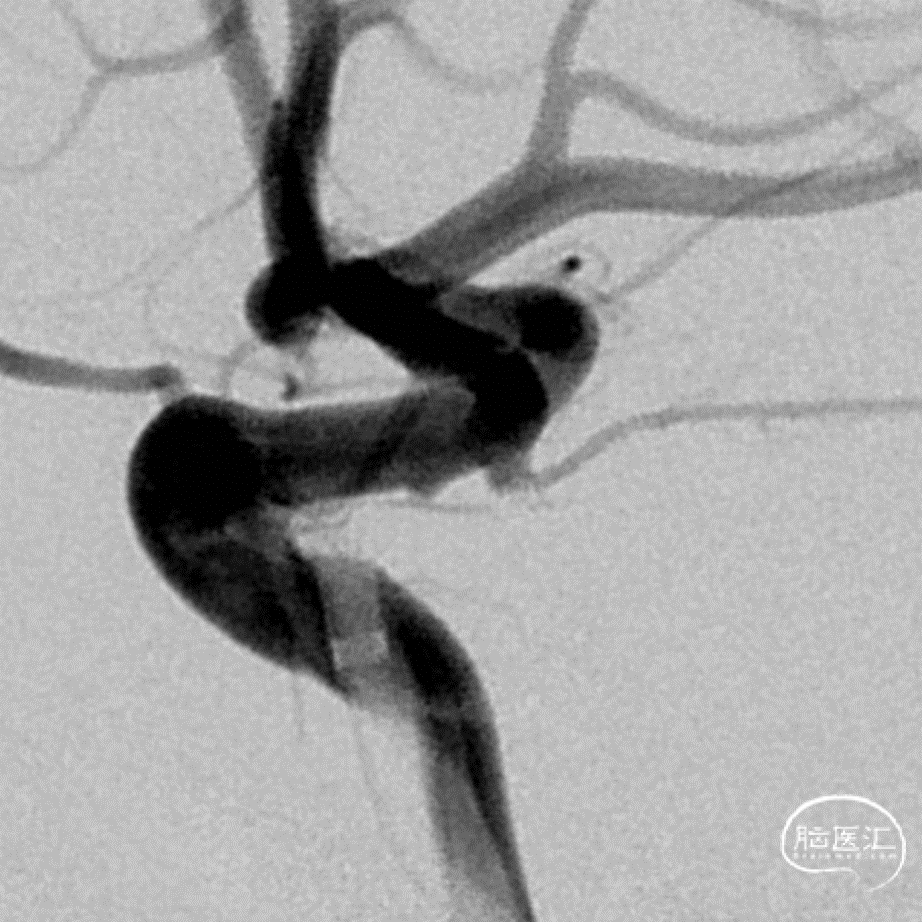

二期治疗

一个月后二期支架(LVIS 3.5mm/15mm)植入

治疗过程

压颈试验

工作角度造影

数值测量

Roadmap

支架远端定位和释放

释放过程

术后即刻

术后即刻支架形态

微导丝按摩

按摩后支架的形态

支架和弹簧圈重建的形态